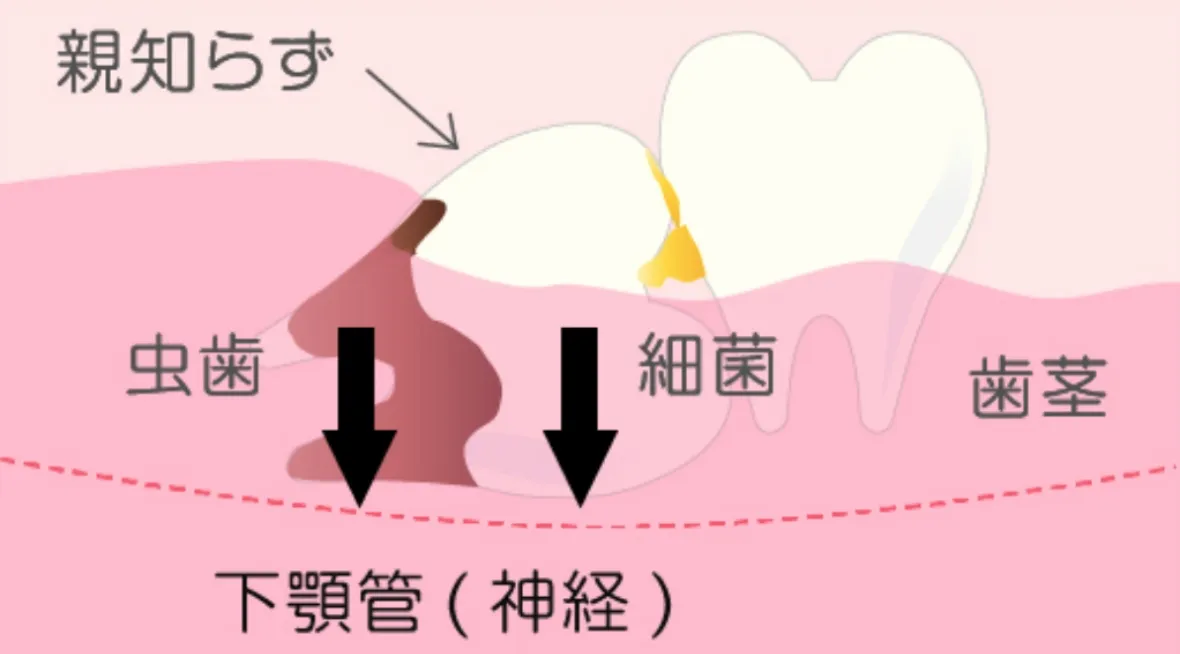

下の親知らずの場合

深く斜めに生えることが多く、歯の隙間の汚れや食べかすで虫歯や歯周病になることがあります。

歯の根は下顎管(かがくかん)という神経に近く、 虫歯や細菌の感染が起きると知覚神経に障害がでる事も。